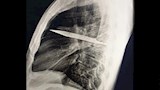

في واقعة طبية نادرة، اكتشف أطباء في تنزانيا شفرة سكين معدنية كبيرة مستقرة داخل تجويف صدر رجل يبلغ من العمر 44 عاما، بعد مرور ثماني سنوات على تعرضه لطعنات متكررة دون أن يعلم ببقاء الشفرة في جسده.

وأظهرت الفحوص السريرية أن الجزء الأيمن من صدره لا يتمدد بالكامل أثناء التنفس، فيما كشفت الأشعة السينية وجود شفرة سكين كبيرة عالقة في تجويف الصدر، ممتدة من الظهر إلى مقدمة القفص الصدري، ومحاطة بطبقات من القيح والأنسجة الميتة.

وتبين أن الرجل تعرض قبل ثماني سنوات لطعنات متكررة في الصدر والظهر والبطن والوجه خلال مشاجرة عنيفة، واكتفى وقتها بتلقي إسعافات أولية للجروح السطحية دون إجراء فحوص تصويرية.